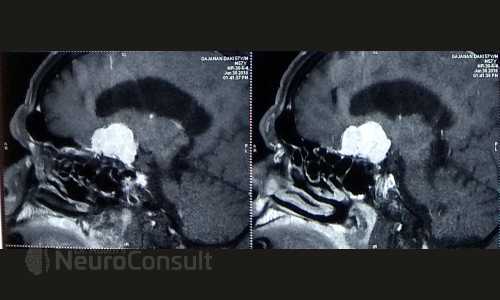

My Cases Studies & Work